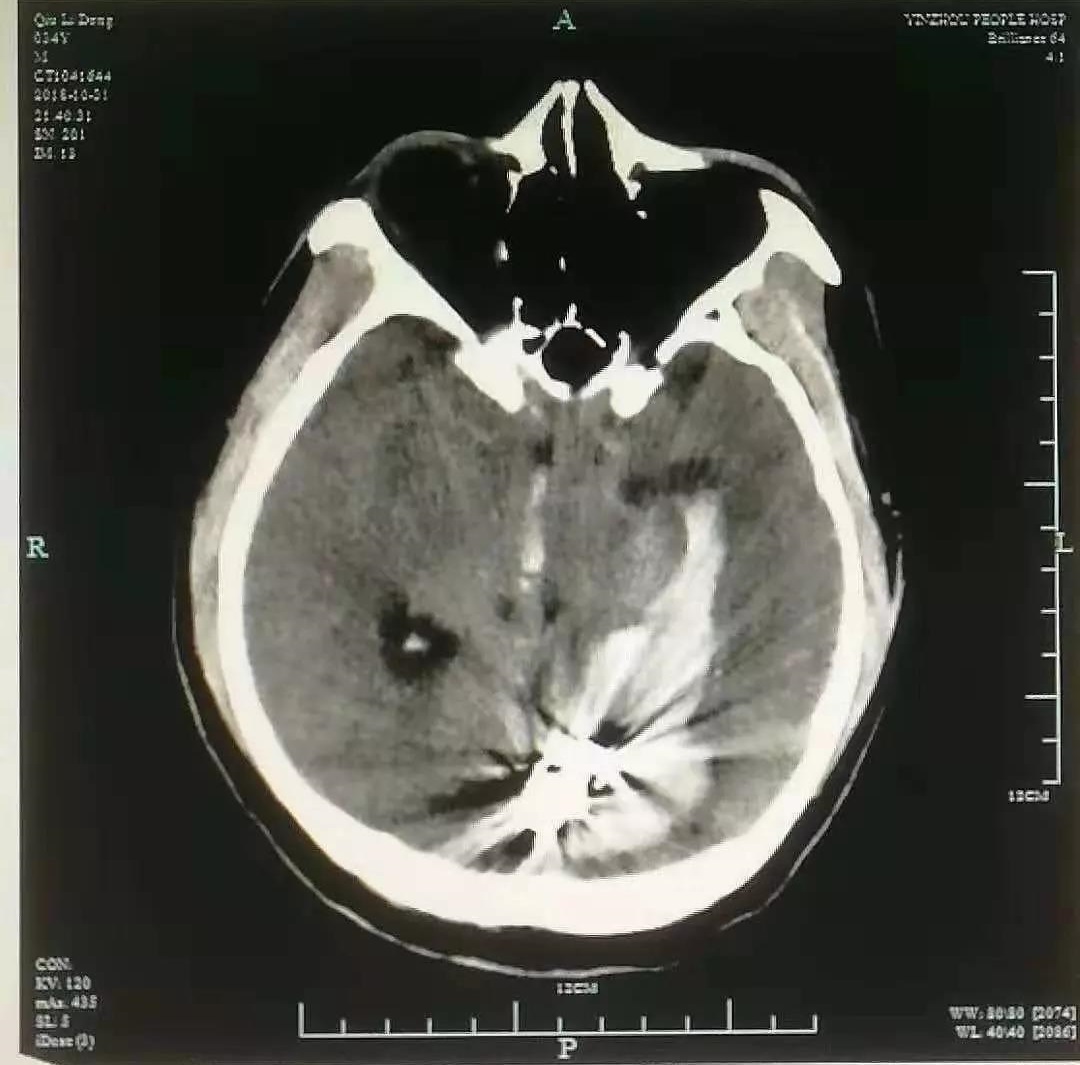

头颅CT显示,小王的左侧枕叶大面积脑出血,出血已破入脑室。该院神经外科主任医师高峰立即为其实施了手术,现在,小王已脱离生命危险。

术前影像